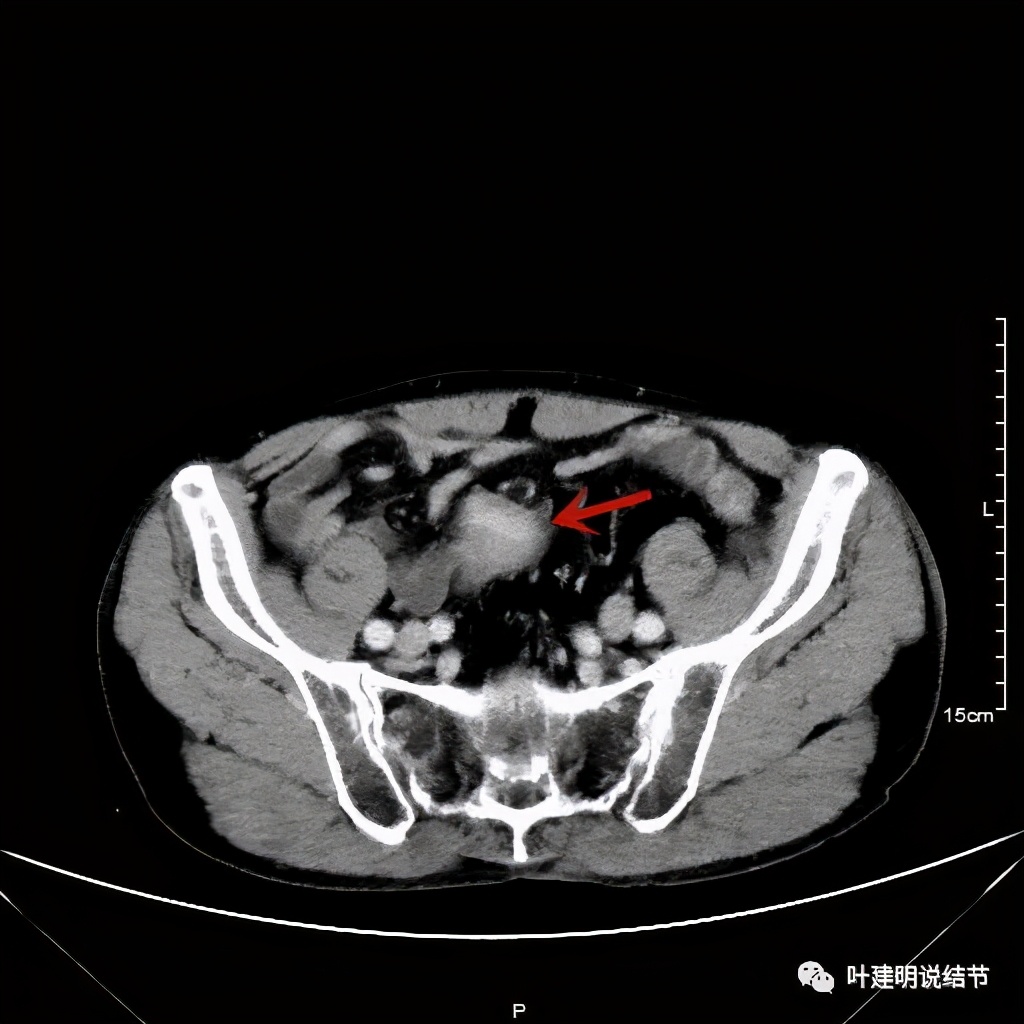

以上诸图红色示乙状结肠肿瘤,绿色示其下方正常的乙状结肠及直肠